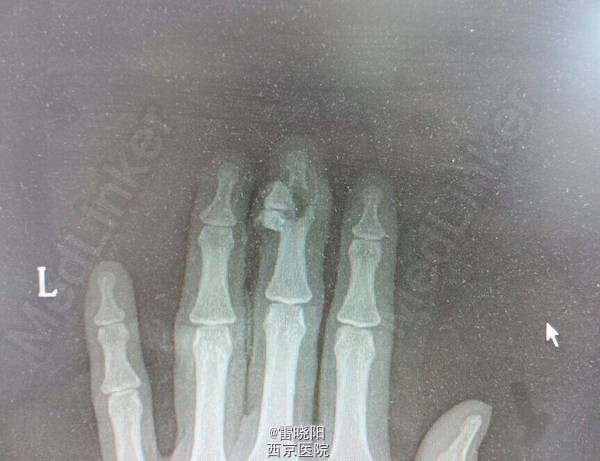

手指贯通伤

患者女,31岁。工作时不慎被药物压片机压伤左手1天